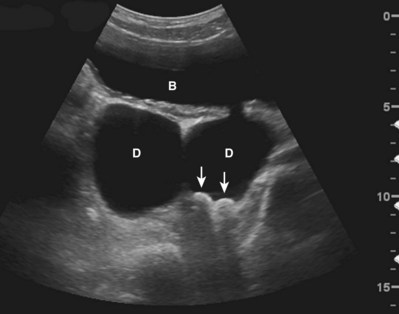

The interaction of ultrasound waves with tissues may produce images that do not reflect the true underlying anatomy. These misrepresentations are called “artifacts.” Artifacts may be misleading but, if recognized, may also assist diagnosis. Acoustical shadowing occurs when there is significant attenuation of sound waves at a tissue interface. Echo information posterior to the interface may be obscured or lost. An anechoic or hypoechoic “shadow” is produced. Under these conditions, three-dimensional objects such as stones may appear as crescentic objects, making it difficult to obtain accurate measurements (Fig. 4–21). Important pathology posterior to such an interface may be missed. This problem may often be overcome by changing the angle of insonation, changing the frequency of the transducer, or changing the focal zone of the transducer.

Figure 4–21 In this transverse view of the urinary bladder (B), there are two large bladder diverticula (D). Two stones (arrows) strongly reflect and attenuate the incident sound wave, producing an acoustical shadow. Note that the stones appear crescentic even though they are ovoid in shape.